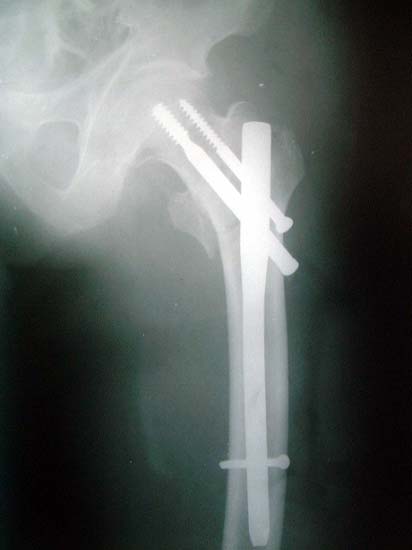

股骨粗隆间骨折,严重移位。            采用闭合复位伽马钉内固定。